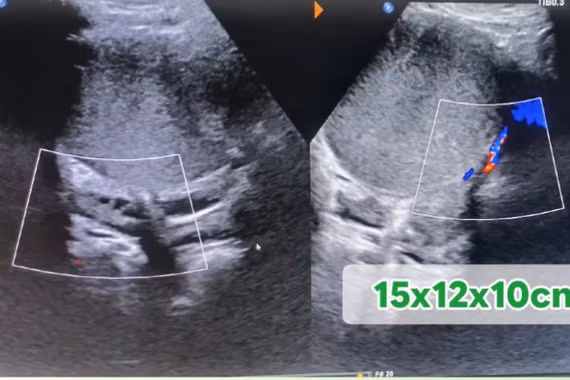

Mới đây, các bác sĩ đã tiến hành xử trí cho 1 trường hợp trẻ nữ 12 tuổi nhập viện do hóc xương gà và 1 trường hợp người bệnh nam 85 tuổi nhập viện do hóc hạt hồng xiêm.

hat-hong-xiem.jpg